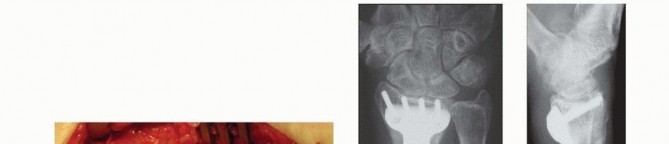

### FIG 2 • A,B. Anteroposterior (AP) and lateral radiographs of extraarticular dorsally angulated malunion. C,D. PA and lateral radiographs of an extra-articular dorsally displaced malunion. E. CT shows rotational deformity associated with a volarly displaced extra-articular fracture. (Copyright Diego Fernandez, MD, PhD.) Lack of motion should be clearly due to malalignment and not due to pain or protectiveness—likewise for instability of the DRUJ. Range of motion: A goniometer is used to measure wrist flexion, extension, radial and ulnar deviation, supination, and pronation. Ulnocarpal compression: The carpus is forcefully ulnarly deviated toward the ulna. Consistent reproduction of usual pain with ulnar deviation tasks is consistent with ulnocarpal impaction. The examiner can test for DRUJ instability by stabilizing the radius and trying to subluxate the distal ulna dorsal and volar from the sigmoid notch of the radius. Substantially, less stability than the opposite side may correlate with symptomatic DRUJ instability, but this is a very difficult and subjective test. Scaphoid shift test: Instability compared to the opposite wrist would indicate a possible scapholunate interosseous ligament tear, indicating a potential dissociative rather than the typical nondissociative carpal malalignment usually associated with distal radius malunion. Grip strength is one of the measure of wrist dysfunction, but it is largely determined by pain and effort—both strongly influenced by psychosocial factors. ## IMAGING AND OTHER DIAGNOSTIC STUDIES PA and lateral radiographs of the wrist ( FIG 2A-D) can be supplemented by specific radiographs for evaluation of the joint surface, particularly for potential articular malunions. Comparison with the opposite, uninjured wrist is useful and serves as a template for surgical correction. CT, particularly three-dimensional CT, is useful to precisely evaluate the joint surfaces ( FIG 2E). Neurophysiologic tests (nerve conduction velocity and electromyography) are ordered to evaluate any symptoms or signs of carpal tunnel syndrome that may need to be addressed. 144 ## DIFFERENTIAL DIAGNOSIS Stiffness: capsular stiffness and tendon adhesions Numbness: idiopathic carpal tunnel syndrome Pain: another discrete source of pain or even nonspecific pain ## NONOPERATIVE MANAGEMENT Nonoperative management is appropriate for low-demand and infirm individuals. Splints are weaned after 6 weeks of cast immobilization. Patients who struggle to regain motion may benefit from working with an occupational therapist or a certified hand therapist. Normal activities are resumed in 3 or 4 months. The patient may return every 2 or 4 months or so until satisfied with the result. Patience is warranted in many situations, particularly for patients with ulnar-sided wrist pain thought to be due to an extra-articular malunion. This discomfort is the last pain to go away after a distal radius fracture and can last up to a year. ## SURGICAL MANAGEMENT Surgery is appropriate when a radiographic deformity correlates with a specific anatomically correctable problem and the deformity is associated with a substantial risk of dysfunction or arthrosis. The patient must understand the risks and benefits of intervening. The surgeon should be wary of pain as the primary complaint because pain is strongly influenced by psychosocial factors, and pain relief is an achievable goal only when consistent with an objective, correctable anatomic deformity such as discomfort clearly associated with a substantial ulnocarpal impingement. When the issue is restriction of motion and there is less than 20 degrees of dorsal tilt or less than 5 mm of ulnar positive variance, a nonoperative approach may be warranted.

### TECH FIG 6 • A-C. PA and lateral radiographs and CT of an intra-articular dorsally angulated malunion. D. A Freer elevator is used under fluoroscopy to reposition the articular fragment. E,F. Intraoperative fluoroscopic views showing provisional correction and fixation. G,H. Final plate and screw fixation. (Copyright Diego Fernandez, MD, PhD.)